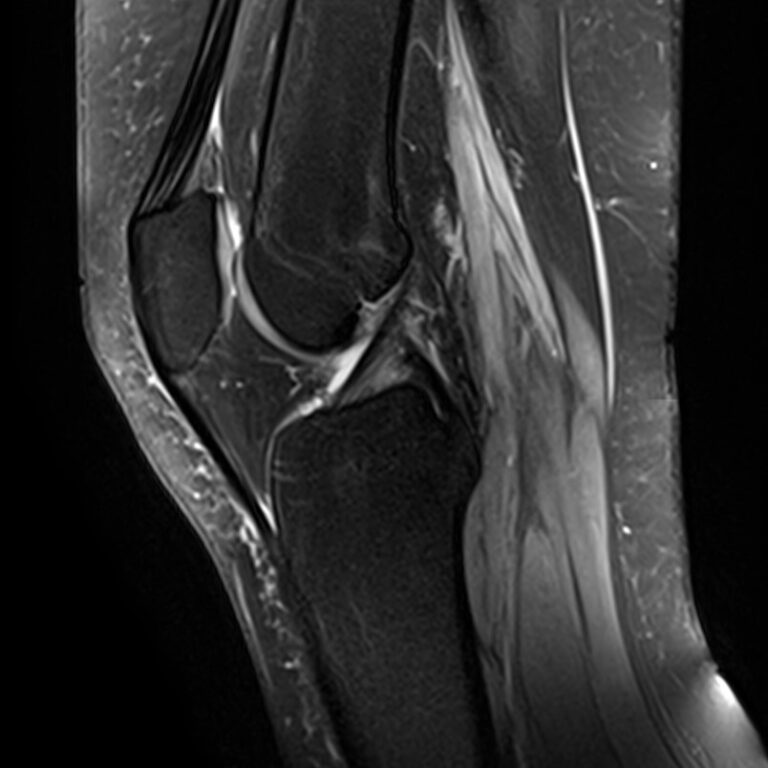

Магнитно-резонансная томография является высокоинформативным методом выявления причин возникновения заболеваний коленного сустава. В клинике «Доступная медицина» диагностика осуществляется на новейшем высокопольном томографе закрытого типа TOSHIBA VANTAGE TITAN 1,5 Тесла, обеспечивающем высочайшее качество изображений исследуемой зоны.

Томограф позволяет детально визуализировать как костные структуры колена, так и окружающие мягкие ткани данной анатомической области, включая мышцы, связки, нервные сплетение, сосуды.